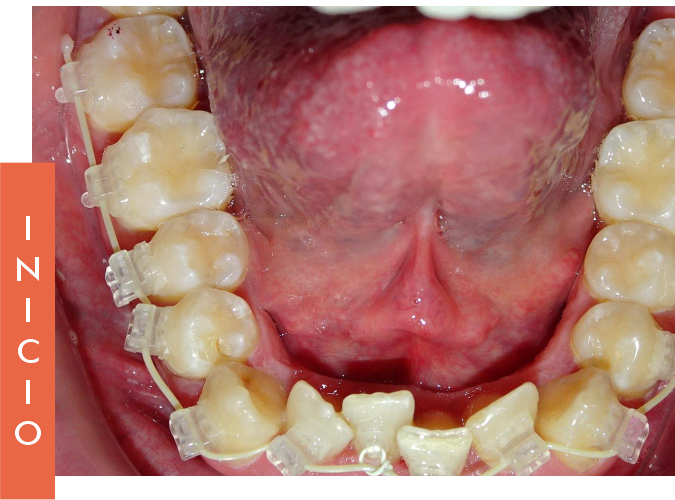

La BTM permite restaurar el Arco Natural Dentoalveolar, mejorando notablemente la estética dental y facial del paciente. Esta filosofía busca devolver una oclusión funcional y estable, respetando la anatomía natural.

Los segundos molares superiores, clave en esta técnica, se mantienen protegidos de fuerzas externas, sirviendo como punto de referencia para lograr una expansión transversal eficaz y controlada.

Esto convierte a la BTM en una herramienta esencial para tratamientos que respetan la biología del paciente.